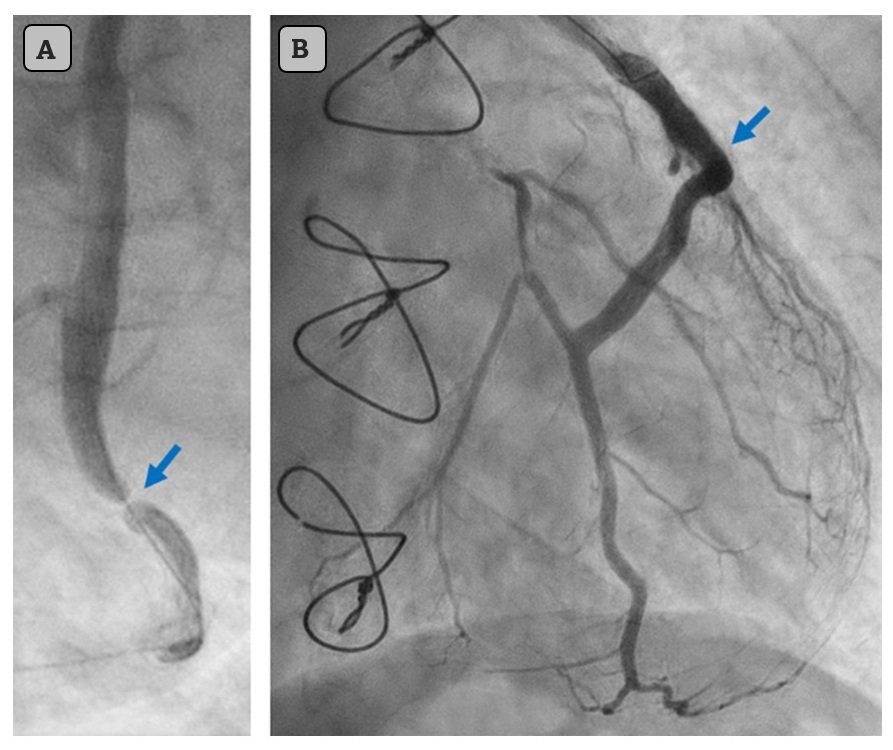

Arrows poiting to the culprit lesion before intervention (A) and after stenting (B).

The culprit lesion was identified as a 99% subtotal occlusion in the venous graft to a large 2nd marginal branch of the LCx, which was treated with stent placement. Peak troponin I reached 40,758 ng/L, and echocardiography showed a posterolateral wall motion abnormality with an ejection fraction of 39%. Frequent PVCs, but no sustained VT was observed following revascularization. Contemporary heart failure therapy was initiated, including slow-release metoprolol 75 mg twice daily.